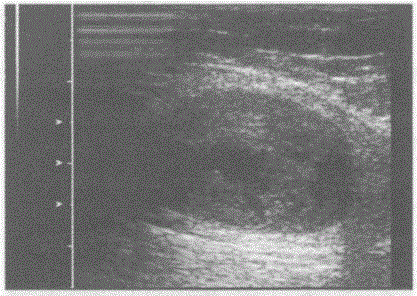

问题 临床资料:男,45岁,自诉右上臂外侧可触及一肿物。 超声综合描述:右上臂外侧肌层内可见不均质低回声,边界清晰,形态规则,加压后形态无明显改变,后方声加强,CDFI:内部可见血流信号。见下图及彩图。 {图1} 超声提示:

选项 A.右上臂纤维瘤 B.右上臂肌腱断裂血肿 C.右上臂血管瘤 D.右上臂横纹肌肉瘤

答案 A